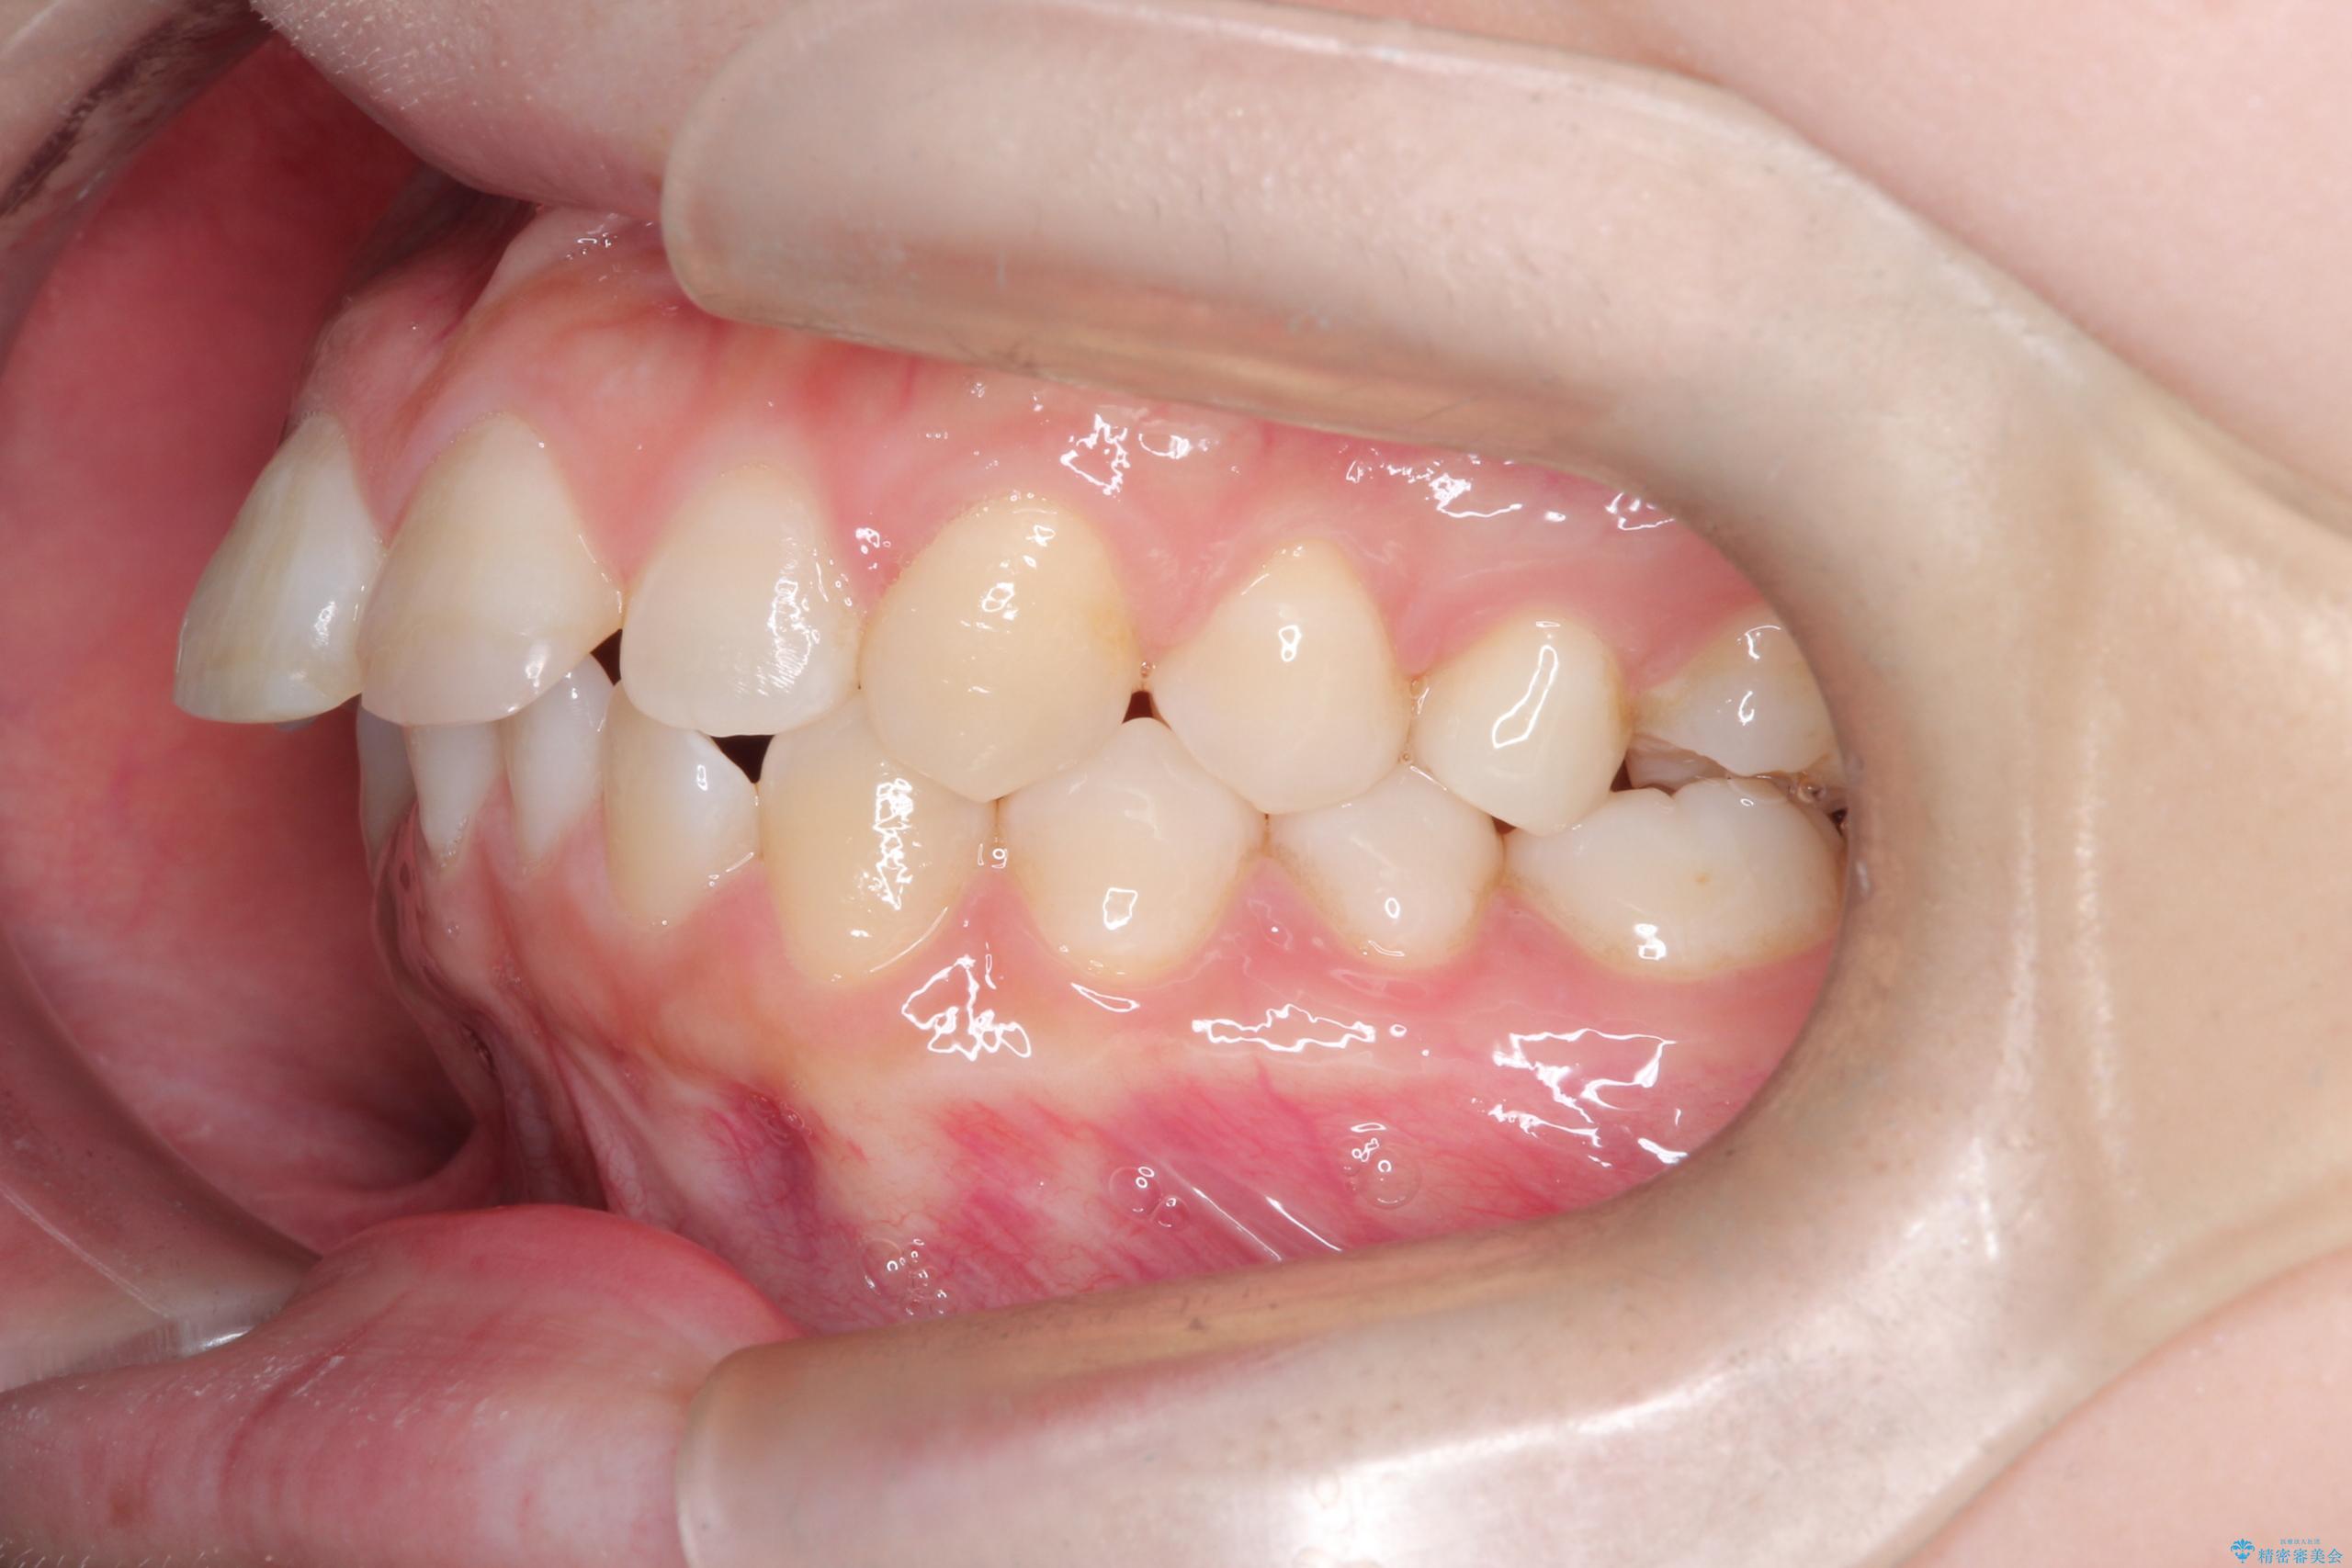

- 前歯のデコボコ(叢生)を気にされてご来院されました。精密な検査の結果、歯が並ぶスペースが不足していることが判明。患者様のご希望から、透明で目立ちにくいインビザライン(マウスピース矯正)による治療計画を立案しました。抜歯を避け、奥歯全体を奥へ動かす遠心移動という方法でスペースを確保し、前歯の叢生を解消することを目指します。

今回の矯正治療では、透明なマウスピース型の装置インビザラインを使用しました。この装置は取り外し可能で、日常生活で目立ちません。治療は、緻密に計算された計画に基づき、段階的に作製されたマウスピースを交換していくことで、奥歯から順に全体を後方へ移動させる遠心移動を実施。これにより、前歯を並べるための十分なスペースが確保され、デコボコが解消されました。抜歯することなく、機能的にも審美的にも整った美しい歯並びを獲得していただけました。